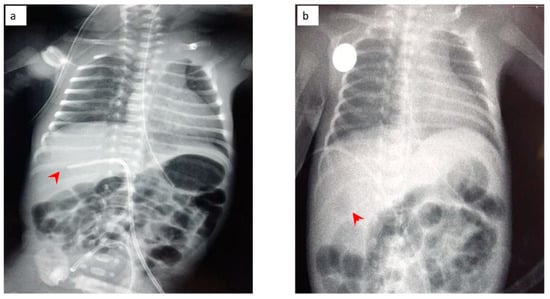

The neonate was then stabilized, and ultrasonography was performed in order to differentiate the possible causes of blood loss. No IVH was confirmed by cranial ultrasonography, while abdominal ultrasonography depicted a hypoechogenic intrahepatic irregular lesion on the right lobe (3.4 cm × 1 cm) (Figure 8a), with hematoma being the possible diagnosis from the radiologist. Chest and abdominal radiography (Figure 9a) showed an abnormal position of UVC, so it was removed. On the following radiography (Figure 9b) air in the branches of right portal vein and hepatic parenchyma was noted (as shown in Figure 9b).

Figure 9.

(a) Chest and abdominal radiography depicting the abnormal position of umbilical venous catheter in the liver (red arrowhead); and (b) chest and abdominal radiography depicting air in the branches of right portal vein and hepatic parenchyma (red arrowhead).